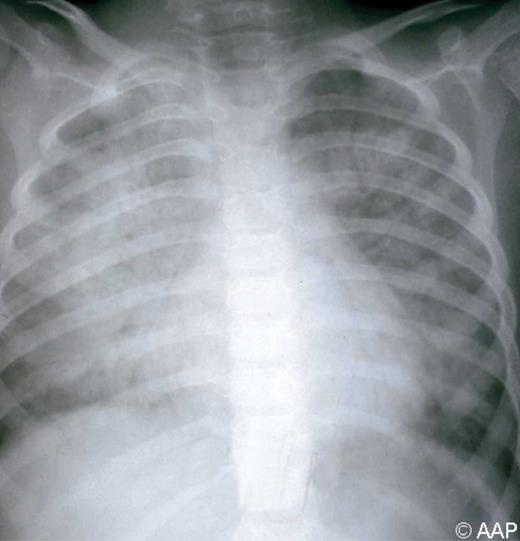

麻疹是一种急性病毒性疾病,其特征是发热、咳嗽、鼻炎和结膜炎,随后出现从面部开始的斑丘疹,并向头尾和离心扩散。在前驱期,可能存在特征性的病原性无花序(Koplik 斑)。麻疹的并发症,包括中耳炎、支气管肺炎、喉气管支气管炎(哮吼)和腹泻,常见于幼儿和免疫功能低下的宿主。急性脑炎通常会导致神经功能缺损,大约每 1000 例中就有 1 例发生。在美国的后消除时代,每 1000 例报告的病例中就有 1 至 3 例死亡,主要由呼吸和神经系统并发症引起。5 岁以下儿童、孕妇和免疫功能低下儿童的病死率增加,包括患有白血病、人类免疫缺陷病毒 (HIV) 感染和严重营养不良(包括维生素 A 缺乏症)的儿童。有时,免疫功能低下的患者不会出现特征性皮疹。